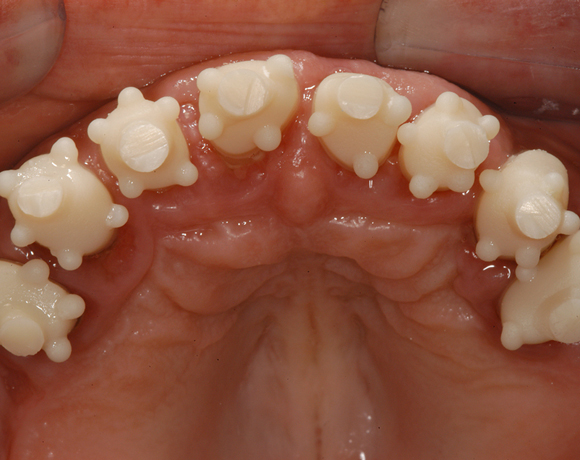

Im vorliegenden Patientenfall musste eine komplette Neukonstruktion der Oberkieferversorgung vorgenommen werden, da auf Grund parodontaler Probleme die Seitenzahnbrücken 15 – 17 und 25 – 27 nicht mehr zu halten waren. Die verbliebenen acht Frontzähne bzw. Prämolaren waren auch parodontal vorgeschädigt und es war ungewiss wie lange sie einzelne noch halten lassen. Um nicht bei jedem Verlust eines der Restzähne eine Neukonstruktion zu brauchen, hat man sich für eine Teleskopprothese entschieden. Für den Patienten war es allerdings nicht vorstellbar goldfarbene Primärteile im Mund zu haben, so wurde der Versuch unternommen diese aus e.max Press und Galvano Sekundärteilen herzustellen.